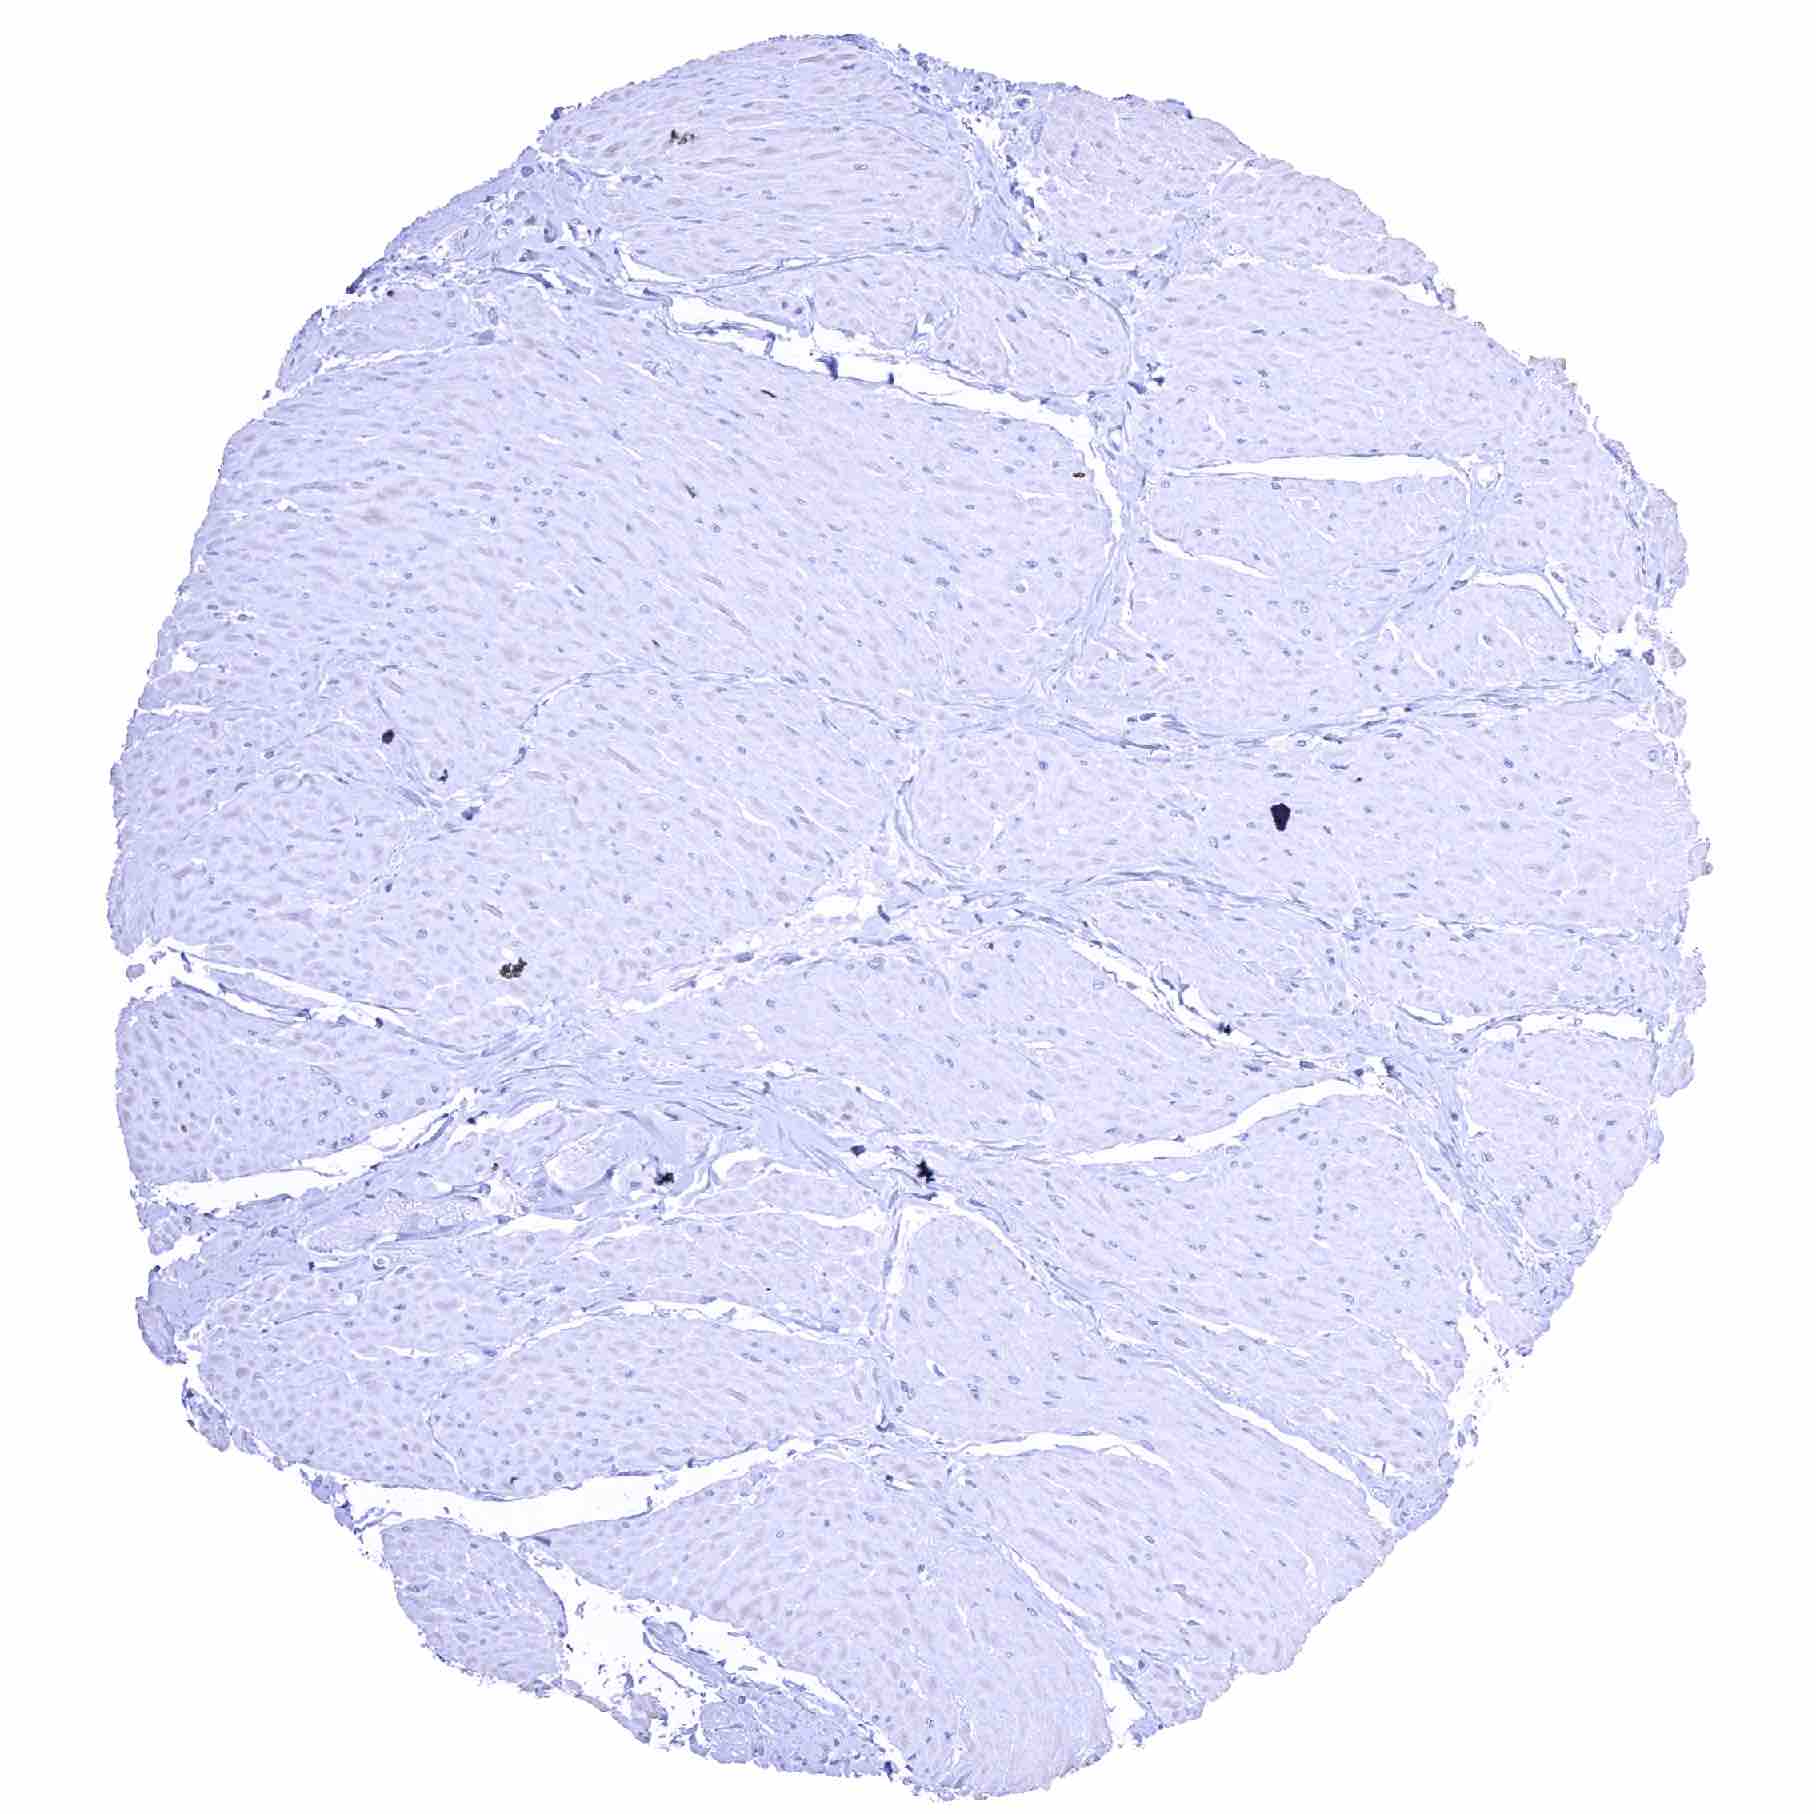

Skeletal muscle